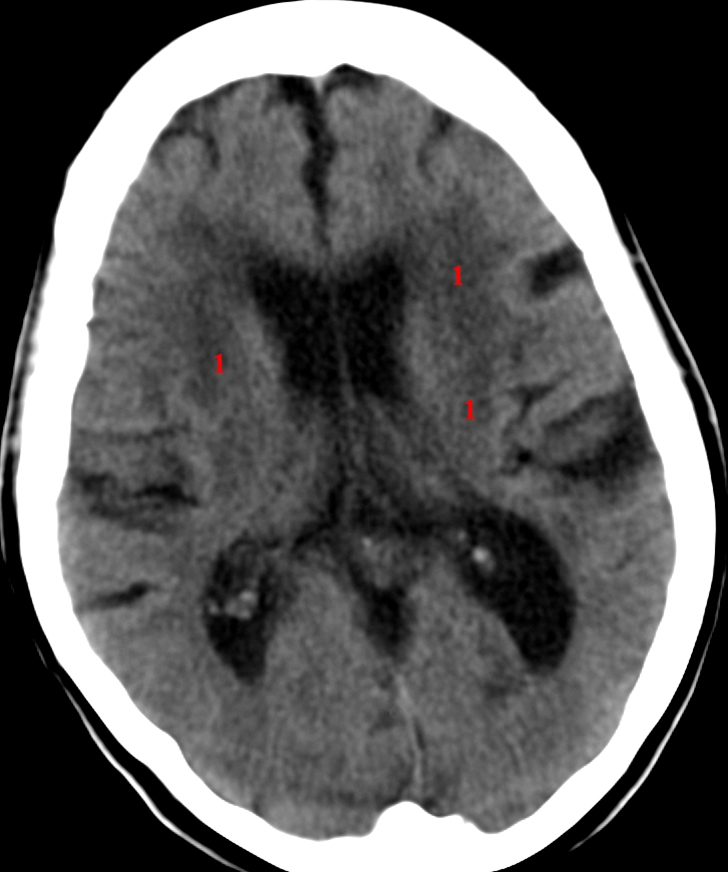

leukoaraiose (CT)

CT cerebrum uden kontrast.

Uregelmæssige, stort set symmetriske, lavattenuerende (mørke) områder (1) på begge sider med vævstab. Skyldes ofte kronisk iskæmi som følge af aterosklerose.

Kan graderes efter udbredelse i Fazekas grad 1-3.